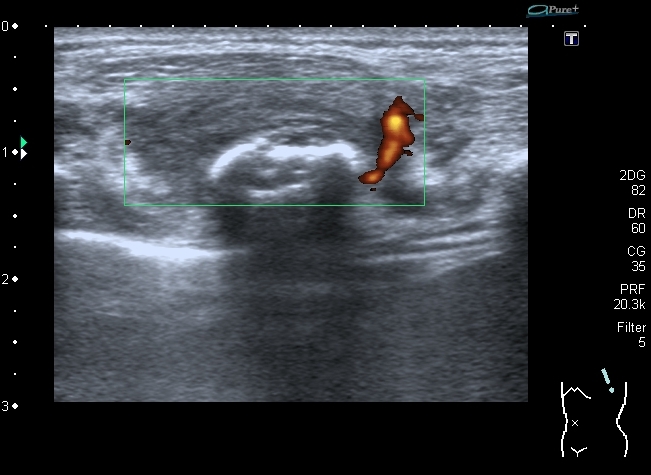

Поперечный скан. Transverse scan

образование оттесняет сосуд,  в самом кровоток достоверно не определяется. No bloodflow in mass is detected.